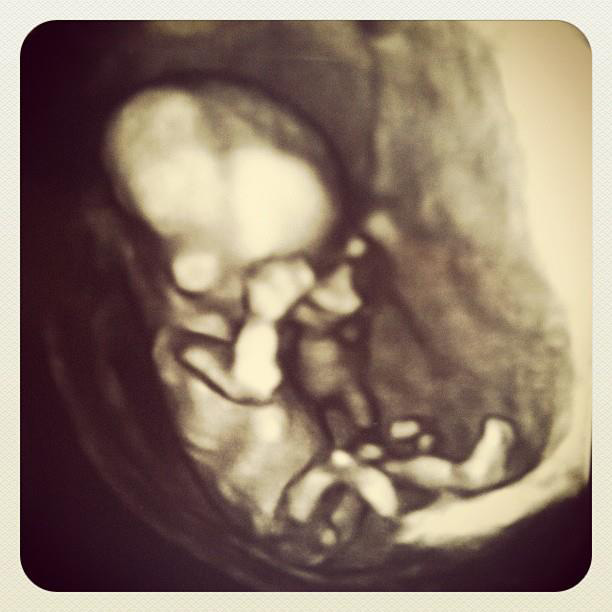

So yeah, we're pretty sure it's a girl. All thanks to this picture:

It was really hard to get my phone in there, but I'm glad I got this Instagram shot. :)

Alright so the ultrasound technology is now so good that it's embarrassingly graphic, right? Like I shared this pic of the ultrasound and then thought... "wait, is this wrong?". I mean, it never in a million years occurred to me that an ULTRASOUND of a 14 week old fetus could be considered graphic, but that's borderline. And again, for those trying to understand what you're looking at... since it's headin' south, that's female. If it was pointing up it would be male. Remarkable to watch this develop. Next ultrasound is May 14th, in which we will announce her name. YAY!